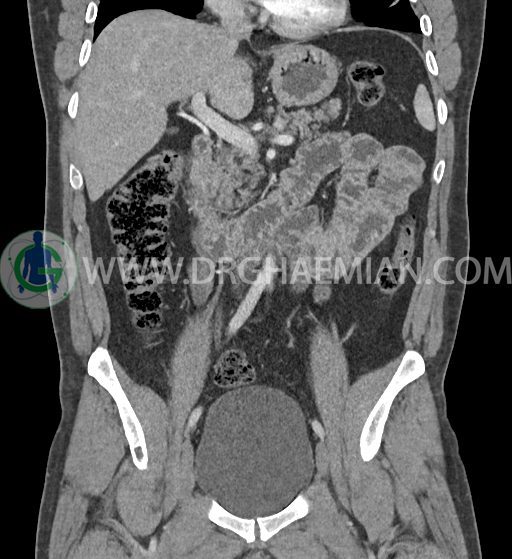

سی تی اسکن شکم و لگن با استفاده از اشعات ایکس تصاویر عرضی از ناحیه شکم و لگن ایجاد میکند. در این کیس فتق هیاتوس و هیدرویورترونفروز دیده می شود.

در سی تی اسکن اسپیرال شکم و لگن با کنتراست خوراکی و وریدی (مولتی دیدکتور 16 با مقاطع ظریف و بازسازی های ساژیتال و کرونال) :

-sliding hiatal hernia به ابعاد 60x44mm با جابجایی JE.junction و فوندوس معده به فضای مدیاستن خلفی دیده می شود.

-هیدرویورترونفروز جزئی دو طرفه دیده می شود که می تواند ثانویه به اتساع مثانه باشد.